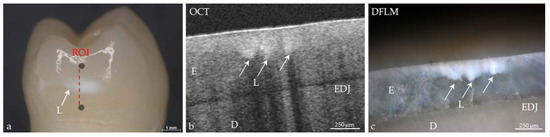

Figure 1. Conformance of visual assessment with optical coherence tomography. (a) Extracted human premolar with a carious lesion (L) of International Caries Detection and Assessment System (ICDAS II) Code 1. The lesion is visually detectable only after drying. Marks define the region of interest (ROI); (b) In the cross-sectional image of the ROI, generated using spectral domain OCT, bright shadowed spots reveal the lesion area is limited to the first half of the enamel (E); (c) After sectioning, demineralization can be imaged using dark-field light microscopy (DFLM) corresponding to the lesion details in the OCT image. D: dentin, EDJ: enamel-dentin junction.

Today the big challenge in caries diagnosis is the detection of very early stages of demineralization, especially in enamel [12,39]. Effective caries management presupposes that these early lesions (represented by porous areas very different in extension) can be reliably recorded. On smooth tooth surfaces, beginning demineralizations can be detected visually as white spot lesions on dried enamel surfaces (ICDAS II Code 1, Figure 1) [3,40], which are a common complication during treatment with fixed orthodontic appliances [41]. At this stage, the subsurface enamel porosity can be stopped or reversed using appropriate non- or minimally invasive therapies and biofilm control [8]. White spot lesions appear whitish as the incident light is backscattered off porous regions to a considerable extent [29,39]. OCT makes use of the same phenomenon. In contrast to the clinical detection solely at the surface, OCT can image structures up to a depth of 2.5 mm and might therefore be a useful supplement to the visual-tactile assessment of tooth surfaces (ICDAS II) and radiography. More reliable differentiation between the really early lesion signs (ICDAS II Codes 0–2) might become possible, irrespective of existing color changes or surface moisture (Figure 1 and Figure 2). Unlike other diagnostic methods, cross-sectional OCT images can present the axial and lateral extension of different demineralized zones (Figure 5).

In vitro studies showed an adequate to strong agreement, when SS- or SD-OCT were compared to histology [29,42,43], confocal microscopy, X-ray microtomography, or transverse microradiography and a diagnostic superiority compared to bitewing radiography [44] (Figure 1, Figure 2, Figure 5, Figure 6, Figure 7, Figure 8, Figure 9, Figure 10, Figure 11 and Figure 14).